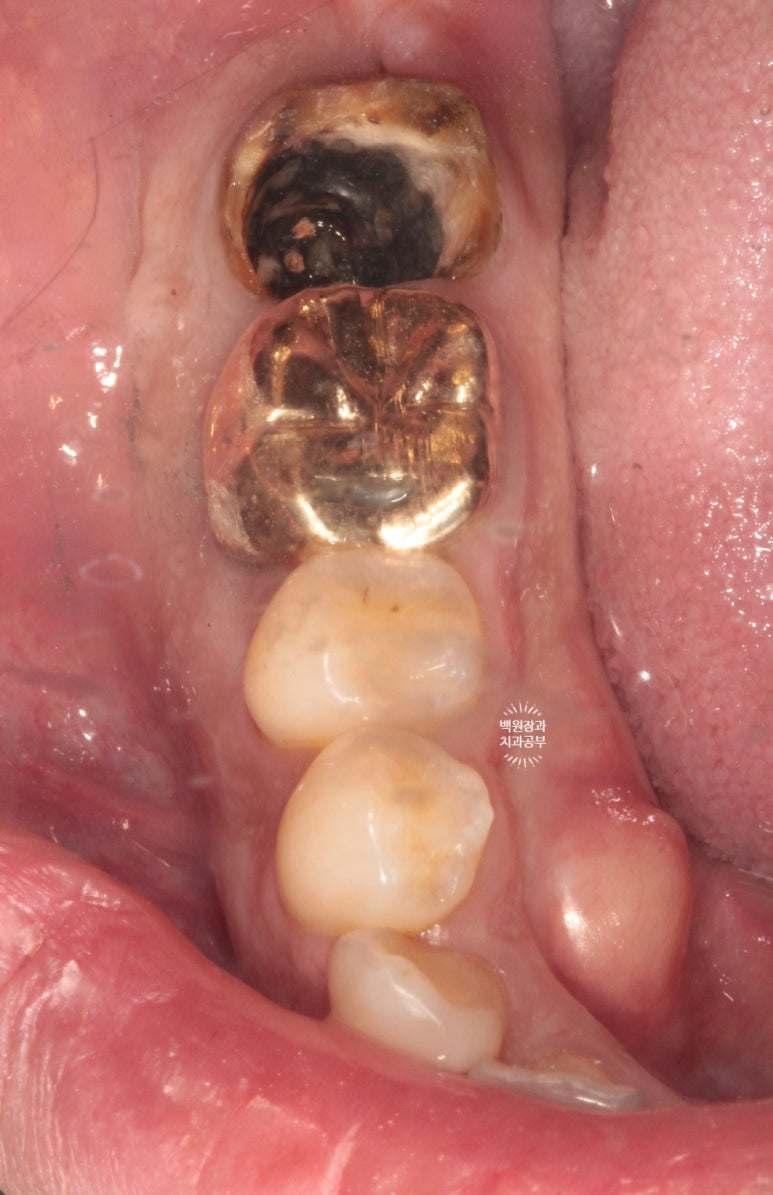

환자분의 사정으로 8주를 기다리고 잇몸뼈 내부를 살펴보았지만, 아직도 치유가 더딘 것이 보이죠?

일단 임플란트를 정위치에 위치시키고, 오스템 임플란트를 사용하여 수술하였습니다.

부족한 부위는 합성뼈로 채워넣었습니다.

저희 연세더좋은플란트치과는 덴티움의 osteon III를 사용하고 있답니다!

오랜 역사와 전통을 가진 국내산 뼈이식재라고 표현하면 알맞을 듯 해요 :) 명품이라고 생각합니다.

그리고 같은 덴티움 사의 dentium collagen membrane (차폐막)을 이용하여 골이식재 상방을 덮어주었습니다.

제대로 된 뼈이식을 하려면 골이식재를 차폐막으로 무조건 덮어주어야 합니다! 말뿐인 골이식재가 아니라 확실한 결과를 얻기 위해선 학문적으로 차폐막의 사용은 필수입니다.

깔끔하게 꿰매드렸습니다.